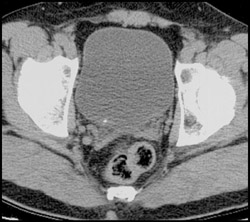

Pyelosinus Extravasation Left Kidney